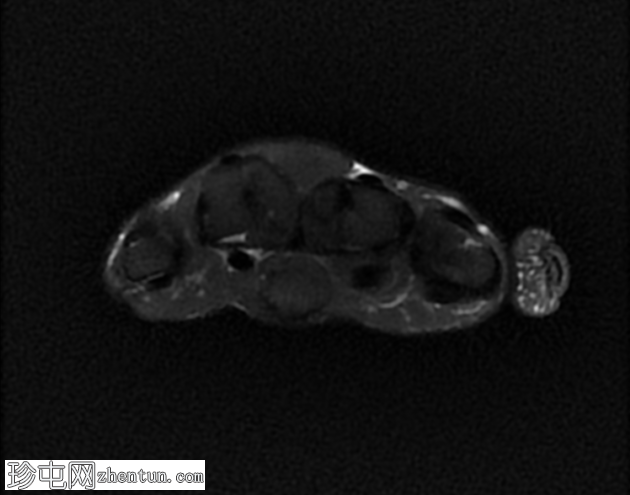

无名指和中指明显增大。患者掌骨和指骨骨质增生肥大,并伴有周围皮下脂肪过度增生。

支配患指的正中神经掌侧支纤维脂肪瘤性错构瘤。它们在矢状面序列上呈现意大利面条状,在轴位图像上呈现绳索状。